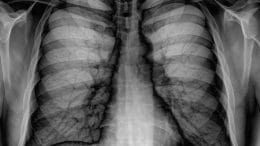

AI And This Mobile Clinic Will Change The Delivery Of Medical Services